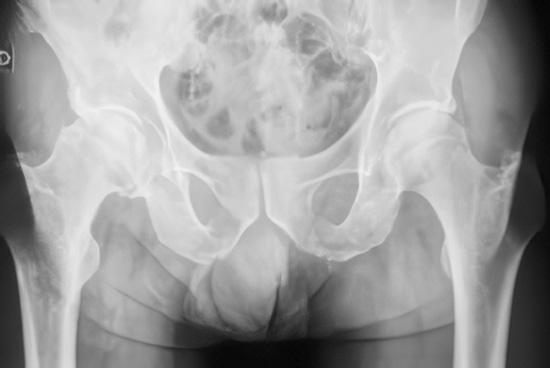

2. Pruebas de imagen

- Radiografías: muestran el estrechamiento del espacio articular, osteofitos, esclerosis del hueso subcondral y deformidades óseas.

- En casos específicos, se puede usar resonancia magnética para valorar el cartílago, la médula ósea o tejidos blandos.